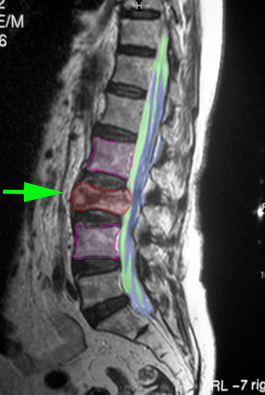

Οπίσθια θωρακοοσφυϊκή σπονδυλοδεσία με βίδες και ράβδους, και πεταλεκτομή, σε ασθενή με ασταθές κάταγμα Ο1 σπονδύλου. |